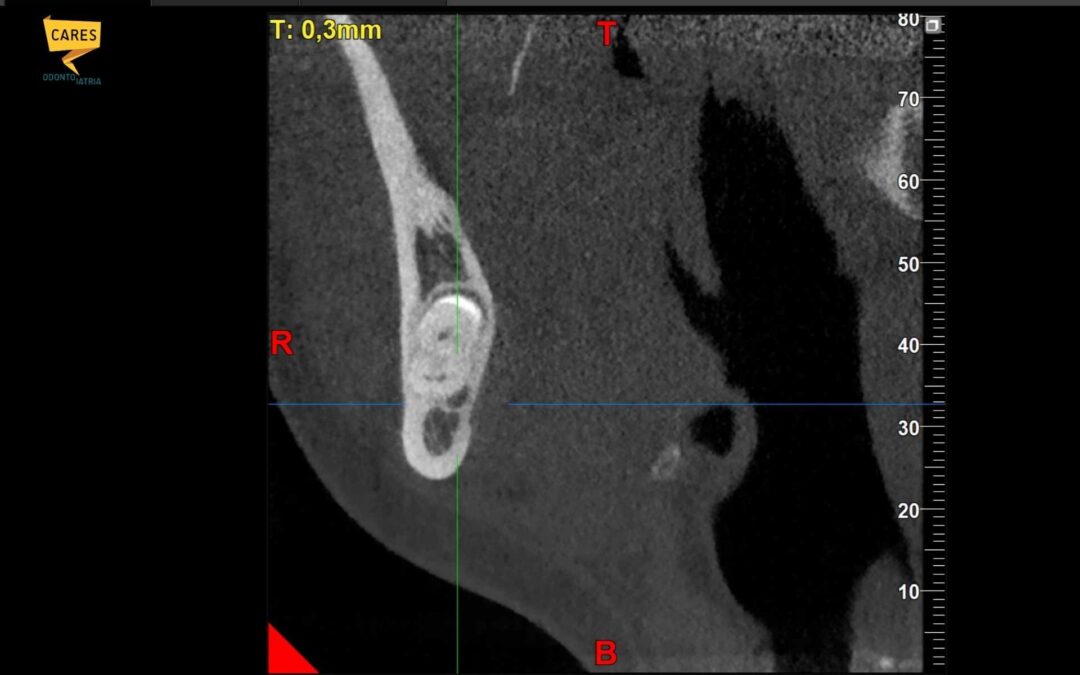

Anche una radiografia panoramica di tutta la bocca è in grado di darci informazioni sullo stato di usura dell’articolazione tra la mandibola e la mascella.